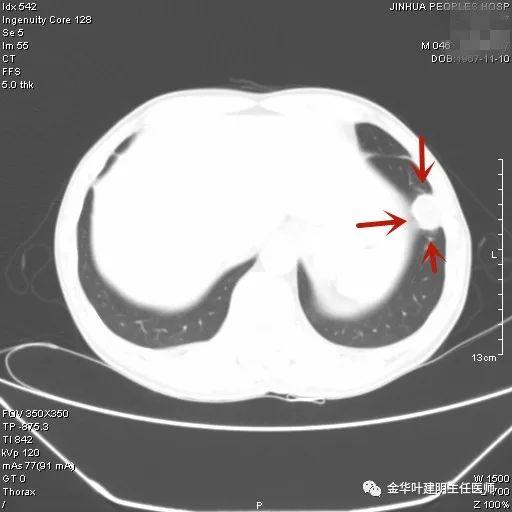

叶建明谈结节:检查发现肺实性结节怎么办?个人版实用指南

上图示鳞癌。病灶厚壁空洞,内壁凹凸不平,鳞癌可以乏收缩力,不一定有毛刺征或胸膜凹陷征。